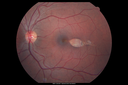

Coats' Disease - 14 year old - Asymptomatic516 viewsPresented with macular exudates. Temporal macroaneurysms responded to laser. Ultra-wide field FA shows nonperfusionNov 07, 2016